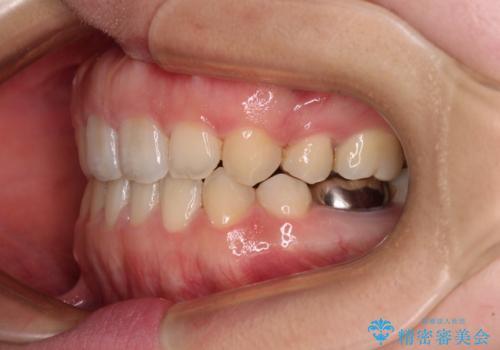

- 口元の膨らみが気になるとのことで来院された患者様です。

非抜歯で口元の突出感を少し改善させる治療も提案しましたが、最大限口元を引っ込めたいとのことでした。

上下左右第一小臼歯4本を抜歯し、ワイヤー装置により矯正治療を行うこととしました。